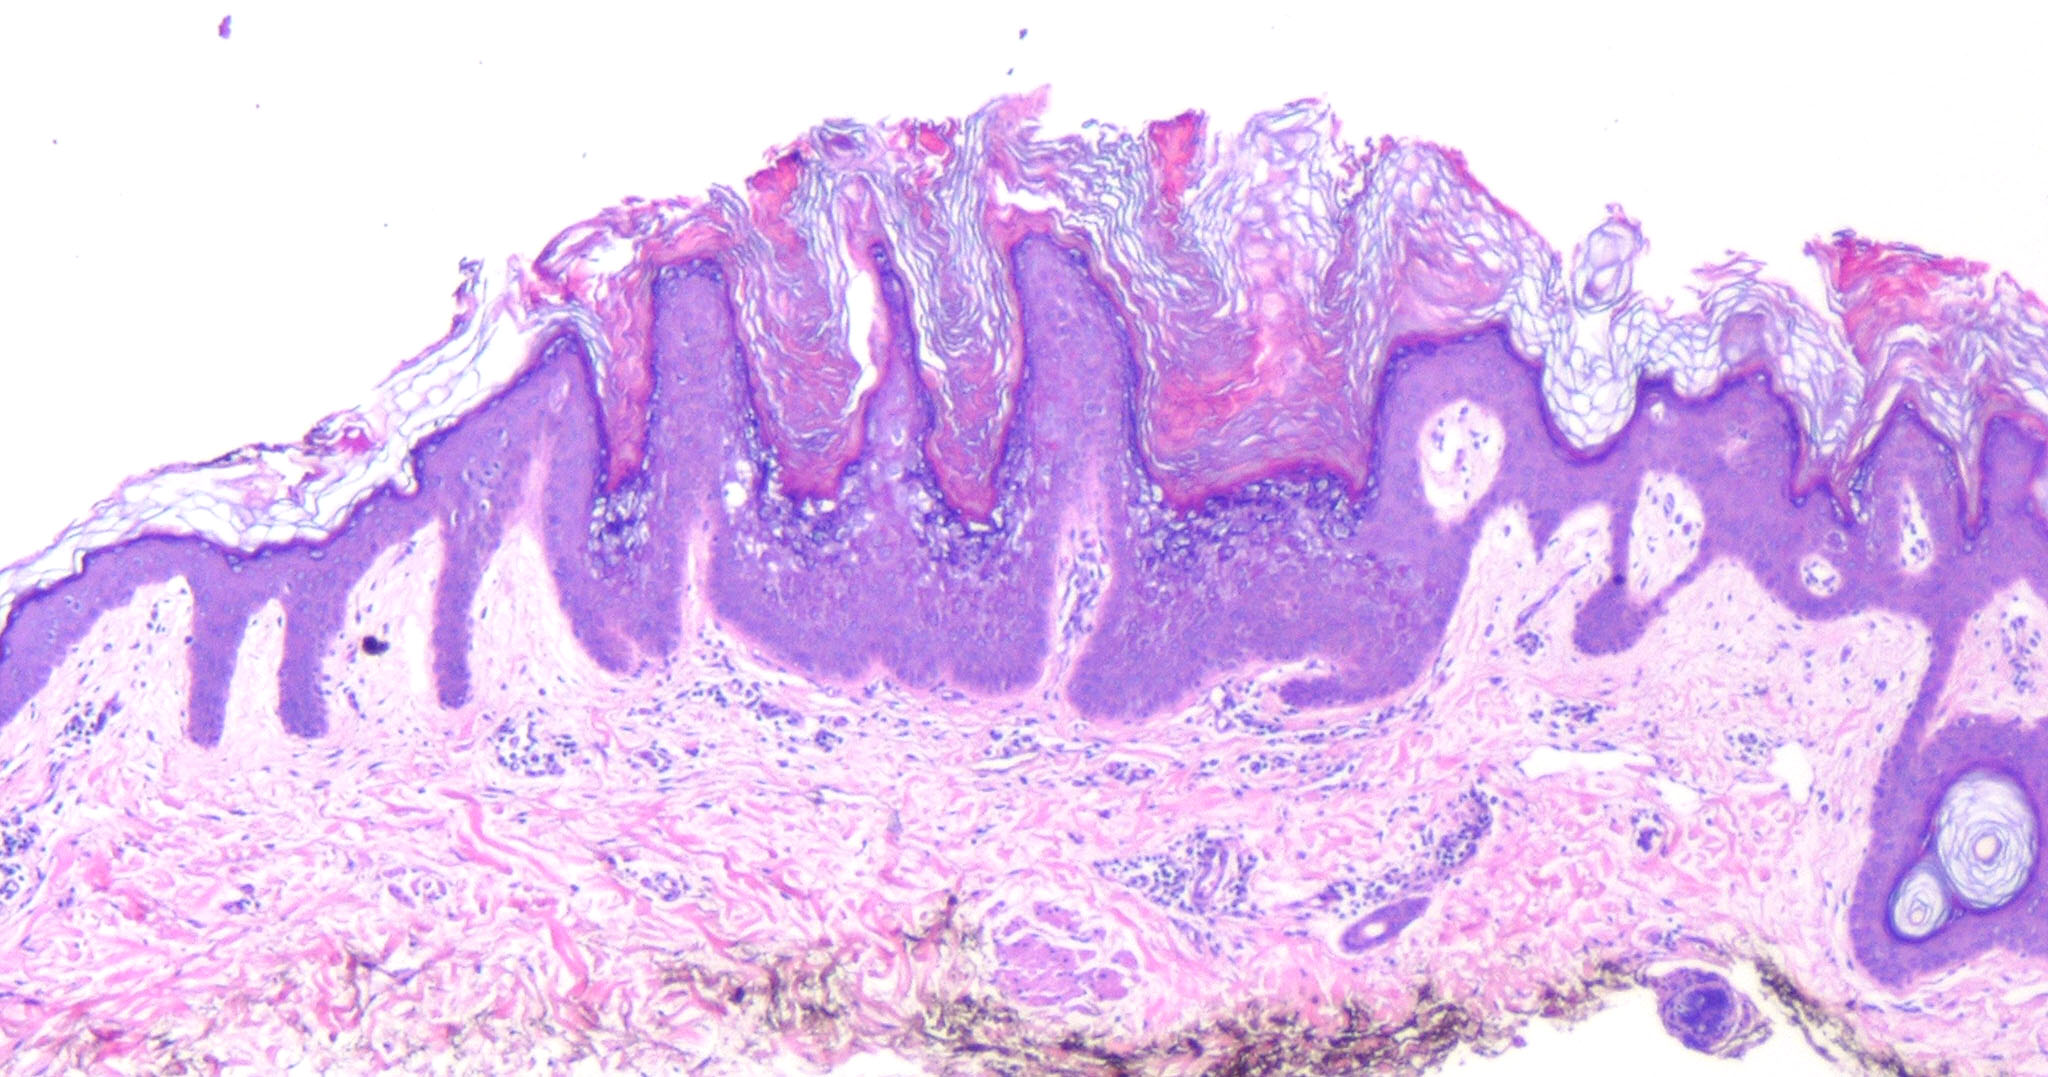

Histopathology. A characteristic histologic picture is seen in the epidermis and is referred to either as epidermolytic hyperkeratosis or as granular degeneration . It is present in bullous as well as in non bullous areas. There are variously sized clear spaces around the nuclei in the upper stratum spinosum and in the stratum granulosum. Peripheral to the clear spaces, the cells show indistinct boundaries formed by lightly staining material or by keratohyaline granules. A markedly thickened granular layer containing an increased number of irregularly shaped keratohyaline granules and compact hyperkeratosis is observed (14). When bullae form, they arise intraepidermally through separation of edematous cells from one another . The upper dermis shows a moderately severe, chronic inflammatory infiltrate. Mitotic figures are five times more numerous than in normal epidermis . Pathogenesis. Defects in keratin genes (KRT1 and KRT10) (16) are now known to be associated with this disorder. Mutations have been found in the carboxy terminal of the rod domain of keratin 1 and the aminoterminal of the rod domain of keratin 10 (17). The essential electron microscopic features are excessive production of tonofilaments and excessive and premature formation of keratohyaline granules; thus, at the periphery of the cells, numerous keratohyaline granules are embedded in thick shells of irregularly clumped tonofilaments (. The desmosomes appear normal, but the association of tonofilaments and desmosomes is disturbed, so many desmosomes are attached to only one keratinocyte instead of connecting two neighboring keratinocytes. Because of this disturbance in desmosomal attachment, blister formation takes place and real acantholysis occurs . Labeling with tritiated thymidine reveals greatly increased proliferative activity in the epidermis . It can be concluded that keratinization is both excessive and abnormal. Differential Diagnosis. Although the histologic picture of epidermolytic hyperkeratosis is diagnostic for the type of ichthyosis called epidermolytic hyperkeratosis, it is not specific for it. Hyperkeratosis is found also in several other seemingly unrelated conditions : epidermolytic keratosis palmaris et plantaris, solitary epidermolytic acanthoma, disseminated epidermolytic acanthoma, and linear epidermal nevus, usually of the systematized type. This latter entity was thought to be an entirely different condition than epidermolytic hyperkeratosis but with similar histologic findings. However, it is now known that epidermal nevi of the epidermolytic hyperkeratotic type are a mosaic genetic disorder of suprabasal keratin (l.e., point mutations of 10k alleles of epidermal cells in keratinocytes from lesional skin) that can be transmitted to offspring producing generalized epidermolytic hyperkeratosis . Epidermolytic hyperkeratosis can be an incidental finding in a variety of conditions